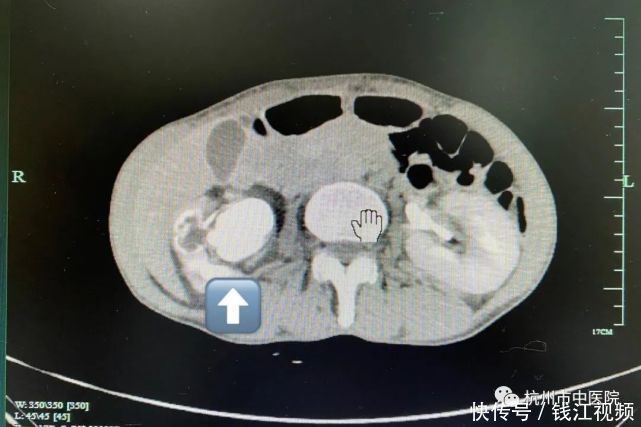

根据CT检查结果提示:王阿姨为右侧肾盏肾盂铸型结石伴右肾积水、右肾体积缩小,更可怕的是,在她的右腹内赫然扫描到了一块巨大到无法直视的结石!结石大约直径6公分,占据了半个肾脏的体积,甚至开始挤压肾实质了,于是科室为王女士行积极抗感染并开始做术前的各项准备。